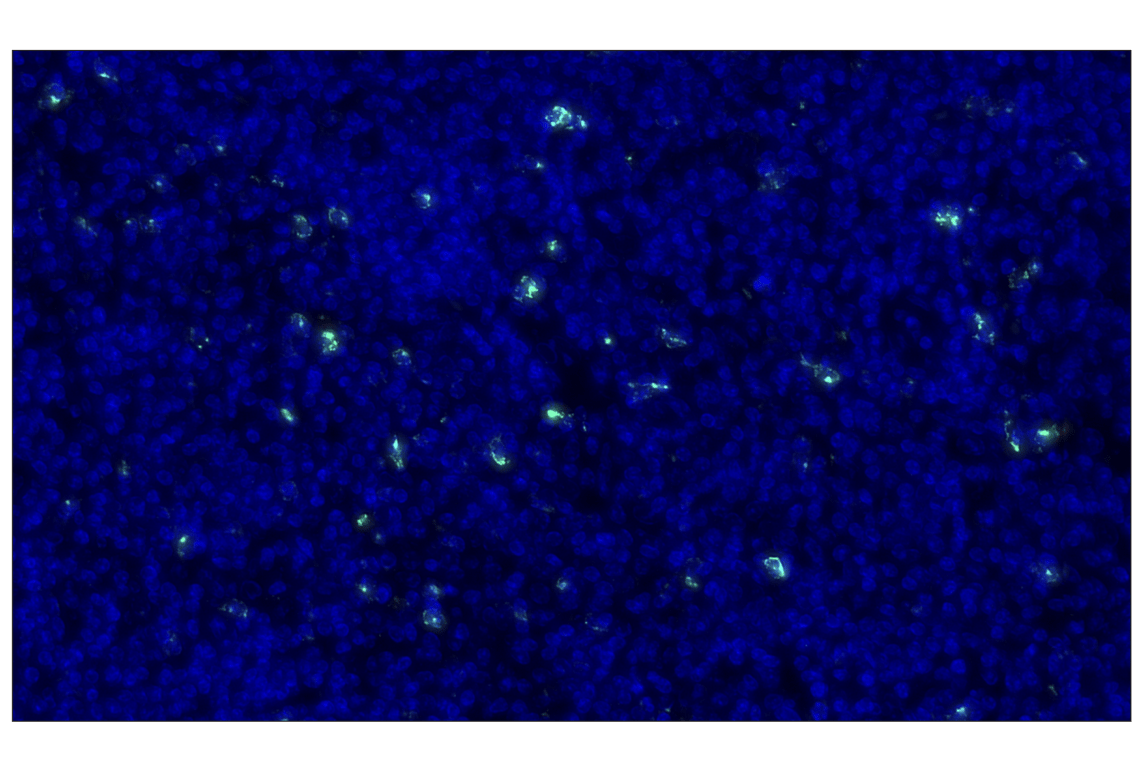

LAG3 (D2G4O) Rabbit Monoclonal Antibody (Alexa Fluor® 488 Conjugate) #35109

This Cell Signaling Technology® antibody is conjugated to Alexa Fluor® 488 fluorescent dye under optimal conditions. This antibody conjugate is expected to exhibit the same species cross-reactivity as the unconjugated LAG3 (D2G4O) XP® Rabbit mAb #15372.

Immunohistochemistry (Paraffin) 1:200 - 1:800

LAG3 (D2G4O) Rabbit Monoclonal Antibody (Alexa Fluor® 488 Conjugate) recognizes endogenous levels of total LAG3 protein.

Human

Monoclonal antibody is produced by immunizing animals with recombinant protein specific to the amino terminus of human LAG3 protein.